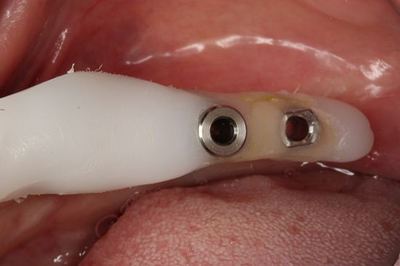

無事埋入を終え、挿入ジグを外しました。

![]()

封鎖スクリュー高さ0.5mmでインプラント上部を封鎖します。

封鎖スクリューで封鎖しました。